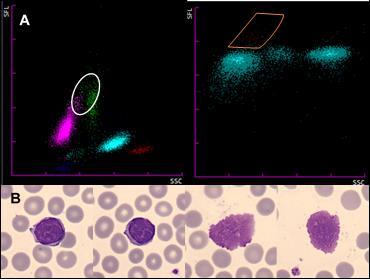

En la Figura 3a podemos observar los scattergramas de un paciente en los que se observa una población de eritrocitos nucleados de 3,6 células por cada 100 leucocitos con una hemoglobina normal (14,1 g/dL; VR: 13,5-17,2) con microcitosis (VCM 71,3 fL; VR: 80-100). Al realizar el frotis de sangre periférica (Figura 3b) se confirmó la presencia de eritroblastos y se observó una serie roja con distribución anormal de la hemoglobina y presencia de abundantes dianocitos. Se descubrió así mismo un cristal de hemoglobina C (marcado en rojo). Tras la realización de un estudio de cadenas de hemoglobina por HPLC, se descubrió una hemoglobina C homocigota y se derivó al paciente a consultas externas de hematología.

Figura 3. a) Scattergramas de un paciente donde se observa una población anormal de eritroblastos marcada en rojo. b) Frotis de Sangre periférica donde se observan eritroblastos (izquierda) y un cristal de hemoglobina C (derecha). Adaptado de: Calvo F, 2019